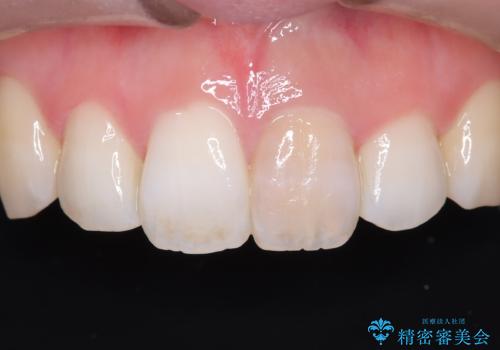

精密な再根管治療: 古い充填材を除去し、歯科用顕微鏡を用いて根管内を徹底的に清掃・殺菌しました。根の先まで確実に薬剤を詰め直すことで、将来的な根尖病変(根の先の膿)のリスクを最小限に抑えました。

オールセラミッククラウンによる修復: 最終的な被せ物には、一切の金属を使用しないオールセラミックを選択。隣の天然歯と色調や透明感を精密に合わせることで、どこを治療したかわからないほど自然な仕上がりとなりました。